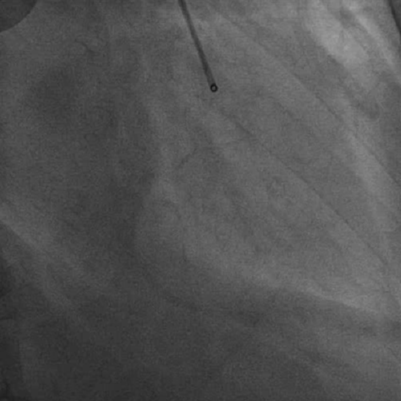

IVUS提示导丝全程位于真腔

逆向导丝换为Pilot150导丝再次尝试,送至RCA中段,透视可见正向逆向导丝非常接近,回撤正向微导管,正向送入2.0球囊至RCA中段后,球囊支撑下送入guidezilla至RCA中段,在RCA中段进行reverse CART,球囊扩张后,逆向导丝reverse CART成功送至guidezilla内。将逆向微导管逐渐跟进到guidezilla内,使用RG3导丝进行体外化。正向使用小球囊对闭塞病变先进行预扩张,使用IVUS验证导丝是否位于真腔。IVUS可见导丝全程位于真腔,斑块负荷非常重。